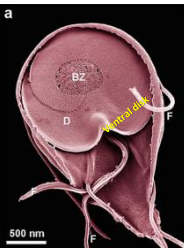

What is the large portion of the Giardia trophozite surface called?

ventral disc

What is the shape of the Giardia trophozite

pear shaped

Describe the structure of the Giardia trophozoite

Two nuclei, 4 pair of flagella, 2 median bodies